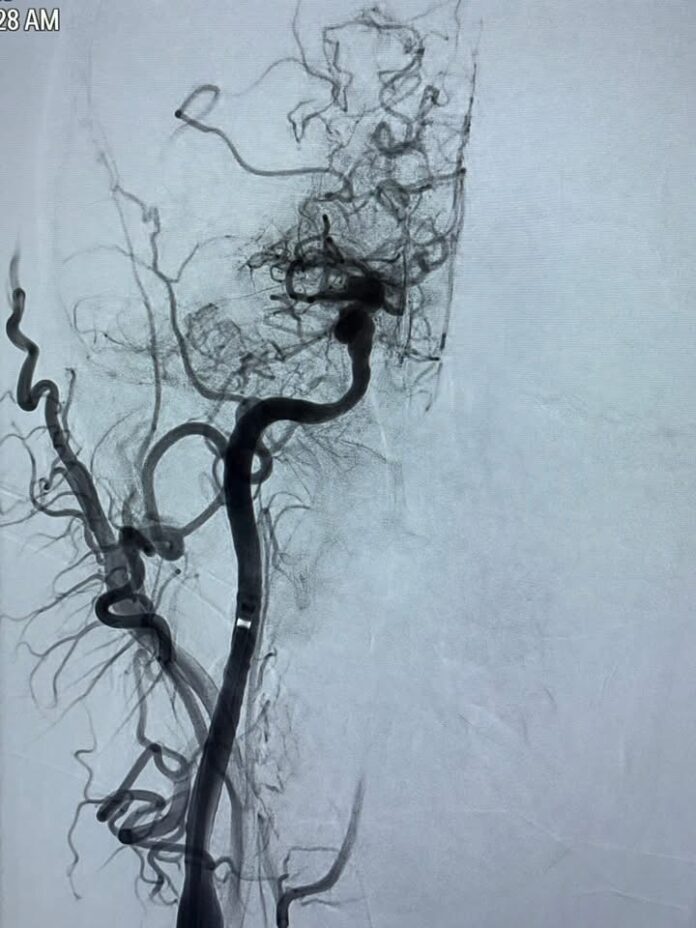

A fost adus de urgență la Spitalul Județean de Urgență „Sf. Ioan cel Nou” Suceava, unde s-a confirmat ocluzia totală a arterelor cerebrale medie (ACM) și anterioară (ACA) pe partea dreaptă.

“Procedura de trombaspirație (îndepărtarea mecanică a cheagurilor de sânge) a fost realizată în mai puțin de 30 de minute, incluzând și timpul de anestezie. S-au extras cheagurile care blocau circulația cerebrală, obținându-se o revascularizare completă — scor TICI 3 (adică restabilirea integrală a fluxului sangvin în arterele afectate)”, a transmis dr. Cătălin Lulciuc, medic primar de radiologie intervențională la Spitalul Clinic Județean de Urgență Suceava.